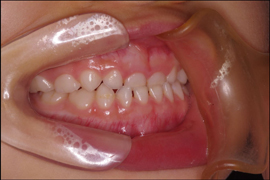

矯正 (男性/中央区)

- 2月24日

- 4月23日

- 6月12日

最初はなれなくて、食べにくかったり口にひっかかったり痛い時もあったけど、抜いてから間がなくなるまで、結構成果が分かりやすく、狭くなっている感じがしてよかったです。

院長のコメント

中学生の患者さんで、下の前歯の叢生(でこぼこ)が気になり、治療を始められました。まっすぐ並べる為に歯を1本抜くことになりましたが、治療始めで4か月弱で終了することができました。綺麗な歯並びになり、歯みがきもしっかりできるようになりました。